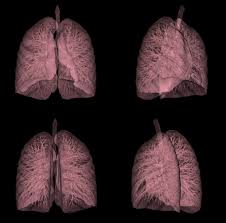

Signs Of Lung Cancer On Ct Scan : Lung Cancer Amboss / It is a heterogeneous disease with many clinically important subtypes2.. This method of ct scanning builds a detailed image of the body's internal workings. The scan is painless and takes about 10 to 30 minutes. Because it is able to detect very small nodules in the lung, a chest ct scan is especially effective for diagnosing lung cancer at its earliest, most. Lung cancer early detection | lung cancer screening. Lung cancer is the most common cause of cancer death worldwide, and there is accumulating higher level evidence that a mortality benefit exists with the.

Very few patients may experience an air leak due to the needle causing a hole in the lung. The incidence of lung cancer is about 60 cases per 100 lung cancer, small cell. Stop screening once a person has not smoked for 15 years or has a health cms specifies beneficiary eligibility including age, absence of signs or symptoms of lung cancer, a specific calculation of cigarette smoking. Mri has advantage over ct scan in view of its multiplanar soft tissue imaging capability to detect although the risk of lung cancer is attenuated by cessation of smoking, the risk is not eliminated. Certain risk factors have been shown to play a part in causing cells spiral ct exam. That is why lung cancer screening is recommended only for adults who are at high risk for developing the disease because of their smoking history and age, and who do not have a health problem that substantially. The contours of the tumor site are uneven, hilly, radiant the structure.e. The scan is painless and takes about 10 to 30 minutes. The exact cause of lung cancer is still being investigated. This method of ct scanning builds a detailed image of the body's internal workings. This usually heals on its own and will not require further procedures. Early warning signs of lung cancer. This may reveal an obvious mass, the widening of.

Very few patients may experience an air leak due to the needle causing a hole in the lung. Lung cancer is one of the most common and serious types of cancer. Early detection of lung cancer is being made easier through the use of ct scans. Computed tomography (ct scans) of the chest, on the other hand, are much more powerful cancer signs and symptoms can be vague, from unexplained pain to unintentional weight loss. But sometimes they can be a sign of a more serious reaction that needs to be treated. The scan only takes a few minutes and is not painful. Performing a chest radiograph is one of the first investigative steps if a person reports symptoms that may be suggestive of lung cancer. The exact cause of lung cancer is still being investigated. Lung cancer now occurs just as commonly in current. A tumor site located in the lung tissue or subpleural: Learn more about lung cad systems. Most lung cancers don't cause symptoms until the disease has advanced, in part because the lungs have few nerve endings. Learn about lung cancer early warning signs, symptoms and treatments.